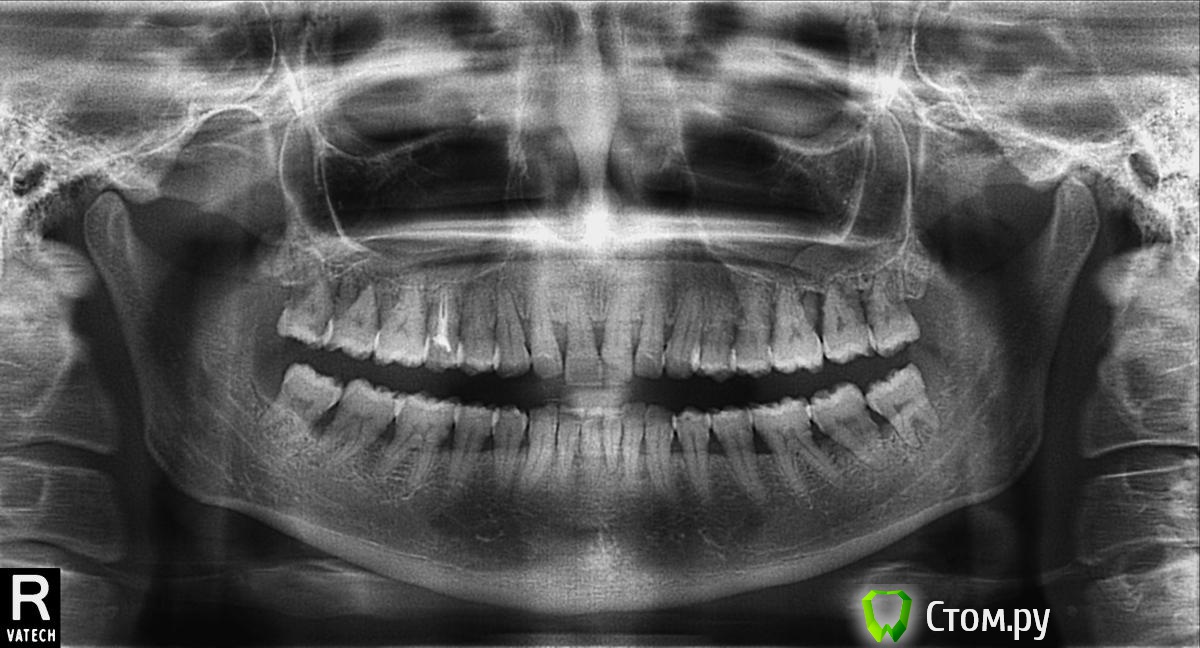

Rumyanceff Опубликовано 31 июля, 2014 Поделиться Опубликовано 31 июля, 2014 Пришла пациентка, с жалобами на боль в обл. 16, 17.17 - подвижность 3 степени, хол.проба отрицательная, 16 - подв. 2 степени, при хол. пробе - резкая боль. Также отмечается подвижность всех зубов в\ч и центрального отдела н\ч. Отправил на ОПТГ.На протяжении нескольких лет чистит зубы лакалютом, парадонтаксом и т.п, периодически делает аппликации метрогил дента, асепта, полоскание кора дуба. Пациентки 30 лет, что делать? Ссылка на комментарий

M@estro Опубликовано 31 июля, 2014 Поделиться Опубликовано 31 июля, 2014 1.6 я бы прицельный поглядел,сомнительный и он. Как мне видится- убрать 3.8 и 4.8 , дабы не усугублять. И далее стабилизировать - парадонтолог + регулярная профгигиена,эндокринолог. Ссылка на комментарий

pulcheriya Опубликовано 28 августа, 2014 Поделиться Опубликовано 28 августа, 2014 Необходимо измерить карманы в шести точках(убыль кости может быть только с одной стороны).Какова рецессия десны?Даже при таком состоянии на панораме,можно продлить жизнь зубам.Начинать в любом случае с открытого кюретажа+мазилки+витамины+антибиотики.И как говорили выше -искать причину. Ссылка на комментарий